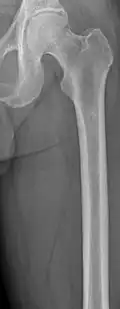

The diagnostic examination of a person with suspected multiple myeloma typically includes a skeletal survey. This is a series of X-rays of the skull, axial skeleton, and proximal long bones. Myeloma activity sometimes appears as "lytic lesions" (with local disappearance of normal bone due to resorption) or as "punched-out lesions" on the skull X-ray ("raindrop skull"). Lesions may also be sclerotic, which is seen as radiodense.[76] Overall, the radiodensity of myeloma is between −30 and 120 Hounsfield units (HU).[77] Magnetic resonance imaging is more sensitive than simple X-rays in the detection of lytic lesions. An MRI may supersede a skeletal survey, especially when vertebral disease is suspected. Occasionally, a CT scan is performed to measure the size of soft-tissue plasmacytomas. Nuclear Medicine Bone scans are typically not of any additional value in the workup of people with myeloma (no new bone formation; lytic lesions not well visualized on nuclear bone scan).

Femur with multiple myeloma lesions -